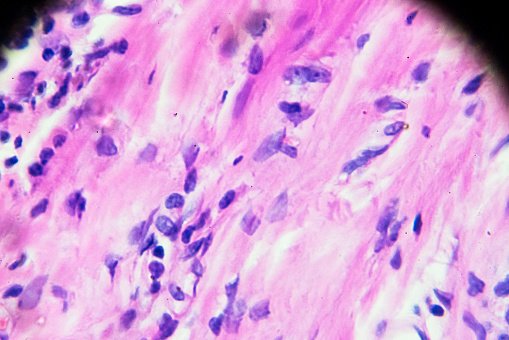

El linfoma es un cáncer de una parte del sistema inmunitario llamado sistema linfático. Existen muchos tipos. Un tipo se llama enfermedad de Hodgkin. El resto se conoce como linfoma no Hodgkin. Más aquí ow.ly/kihE50wTMdG